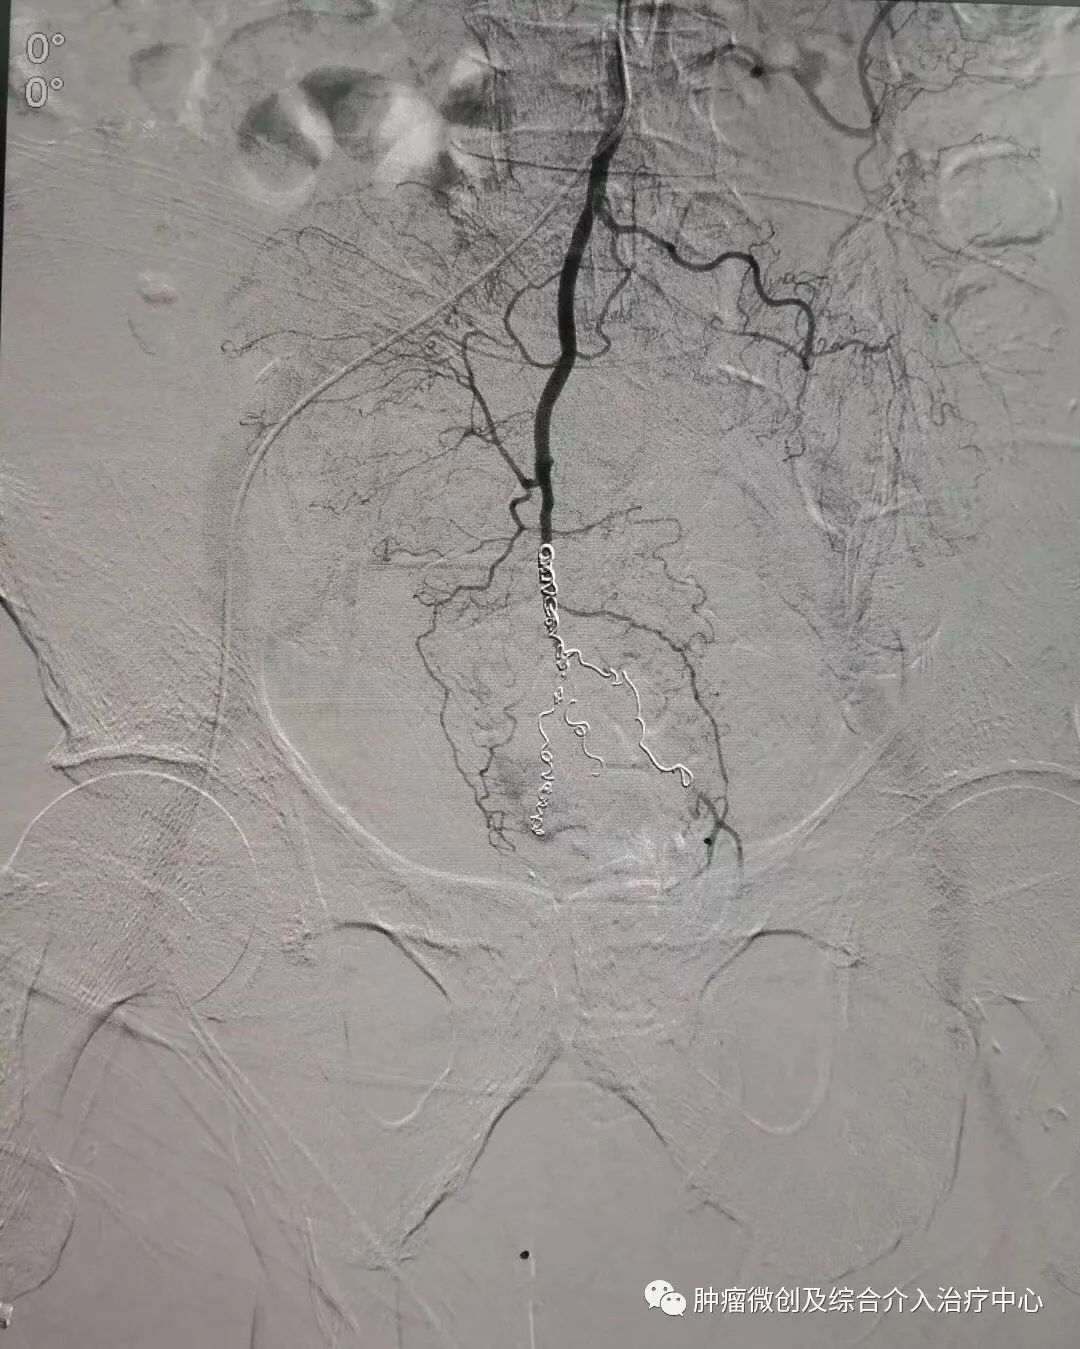

(术前DSA造影提示支气管动脉增粗、增多、絮乱,床表现为咯血,经久不愈)

(介入栓塞术后造影提示支气管动脉走向规则,清晰,术后咯血症状停止)